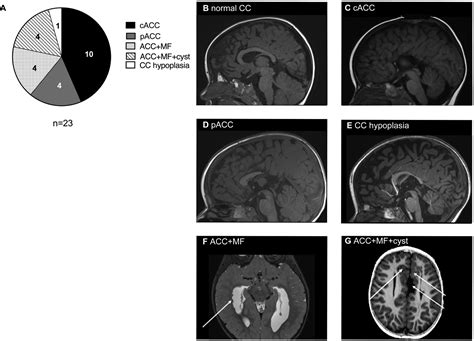

Corpus Callosum Agenesis is a congenital condition, meaning it is present at birth. It can occur as an isolated condition or as part of a broader syndrome. The severity of symptoms can vary widely among individuals, ranging from mild to severe. The condition is often diagnosed through imaging techniques such as magnetic resonance imaging (MRI), which can clearly visualize the absence or underdevelopment of the corpus callosum.

Diagnosis typically involves a combination of clinical evaluation and imaging studies. MRI is the gold standard for diagnosing Corpus Callosum Agenesis, as it provides detailed images of the brain’s structure. Additional tests, such as electroencephalography (EEG) for seizure monitoring and genetic testing, may also be conducted to identify underlying causes and associated conditions.

• Neuroimaging Techniques: Developing advanced imaging techniques to better visualize and understand brain structure and function in individuals with Corpus Callosum Agenesis.

• corpus callosum dysgenesis

• corpus callosum agenesis mri